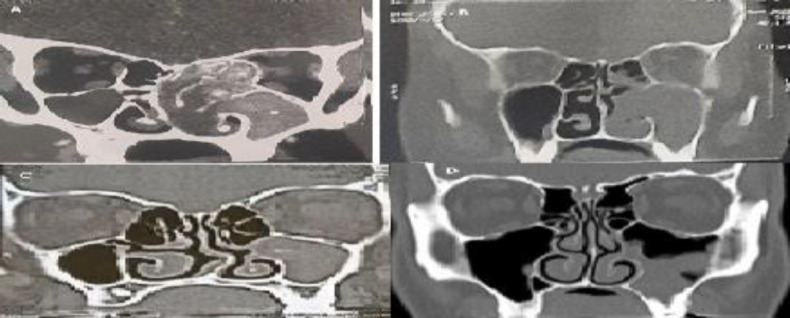

Results: In pediatric patients, the most common inflammatory pathology was antrochoanal polyps, followed by allergic fungal sinusitis. On the other hand, chronic sinusitis without nasal polyps is the most common in adults, followed by antrochoanal polyps. The mean duration of clinical manifestations before diagnosis in pediatric patients was significantly shorter than that in adults (P=0.001). The most common symptoms in both pediatric and adult patients were anterior nasal discharge and nasal obstruction. Proptosis was significantly higher in pediatric group than in adult group (P=0.015). On computed tomography (CT), the most commonly affected sinus in both pediatric and adult patients was the maxillary sinus followed by the anterior ethmoid sinus. Bone expansion, erosion and involvement of adjacent structures were significantly higher in pediatric patients (P=0.028, 0.027 respectively).